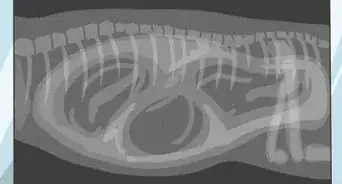

2Know when to take your dog to the vet. Symptoms of false pregnancy will usually go away within three weeks, but if your dog shows them for longer, you may want to take her to the vet. The vet will clinically examine your dog and take any mating possibilities into account to confirm a case of false pregnancy. Other diseases, like late pregnancy, can also be ruled out. If your vet is unsure of a diagnosis, an ultrasound or radiographic test can confirm the condition.